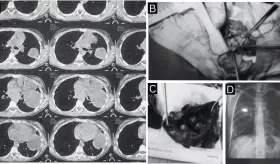

Más de 180 tipos de saborizantes en productos de vapeo pueden generar sustancias tóxicas al ser calentados, lo que aumenta el riesgo de daño pulmonar.